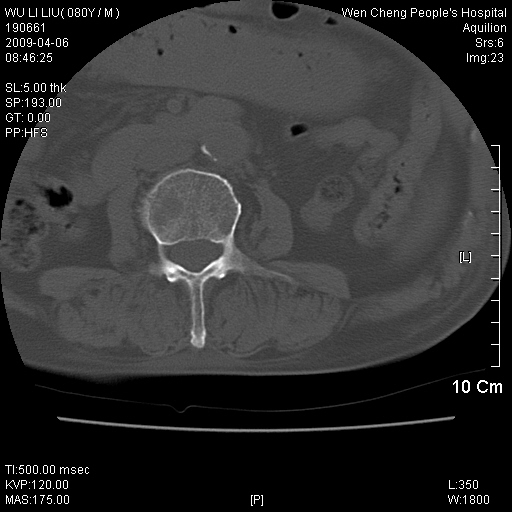

以下是引用zjzjr在2009-4-7 12:13:00的发言:[br]支持多发性转移瘤,右股骨颈骨折,腰椎亦有压缩性骨折.肝内胆管结石伴胆内外胆管扩张,左肾结石.

以下是引用liaoqiang在2009-4-7 8:44:00的发言:[br]考虑多发性骨髓瘤伴肝肺转移、肝内胆管结石、左肾结石、右股骨颈骨折。

以下是引用余辉在2009-4-7 8:52:00的发言:[br]椎骨及骨盆骨质疏松,骨破坏主要累及椎体,各骨破坏较广泛,各病灶边缘均较清晰锐利,血沉增快,白细胞增高.支持考虑多发骨髓瘤,建议查本尿周氏蛋白.[br]胆内胆管及左肾结石[br]右股骨颈骨折,考虑病理性